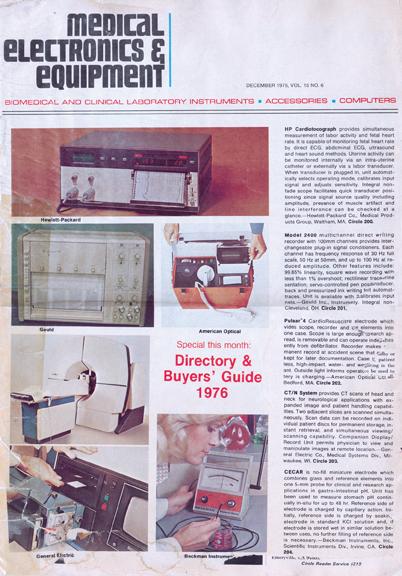

Over the last decade, the field of medical imaging has evolved from analog technology toward the digital age. This shift in medical imaging has seen the emergence of flat panel detector (FPD) technology in everything from cardiology systems to portable X-ray equipment. Digital solutions have already begun to revolutionize medical imaging by offering improved image quality, faster processing time and dose reduction advantages over their analog predecessors. Those who have already adopted digital imaging are part of a market that continues to grow, expected to reach a sum of more than $35 billion by 2019.